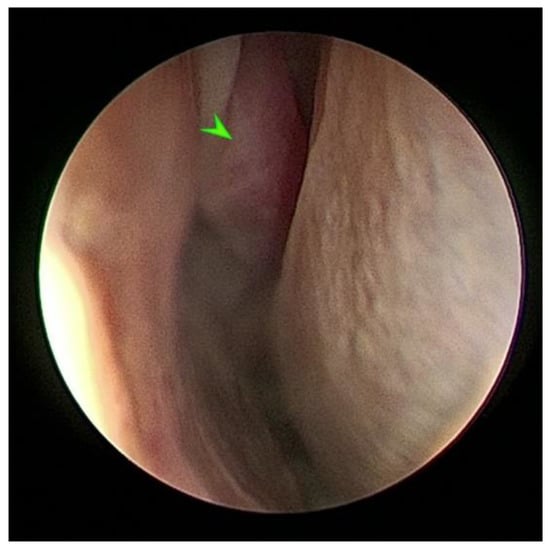

2.2. Endoscopic Sinus Surgery with Biopsy and Tissue Histopathology

2.5. Endoscopic Sinus Surgery with Fungal Mass Excision, Fungal Identification and Medical Treatment